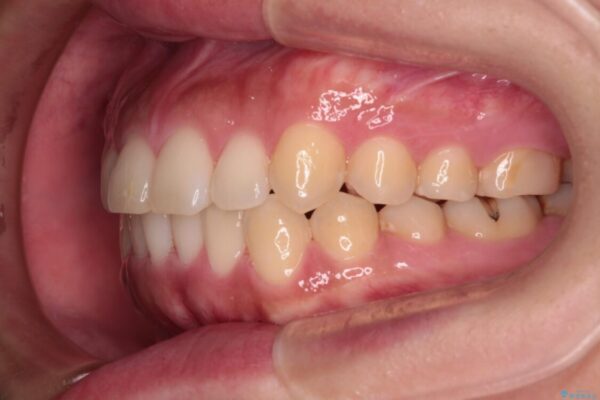

前歯の叢生と八重歯を気にして来院された患者様です。

治療前

• 【モニター】カリエール・ディスタライザーを併用した八重歯のインビザライン矯正 治療前画像

治療途中

• 【モニター】カリエール・ディスタライザーを併用した八重歯のインビザライン矯正 治療途中画像